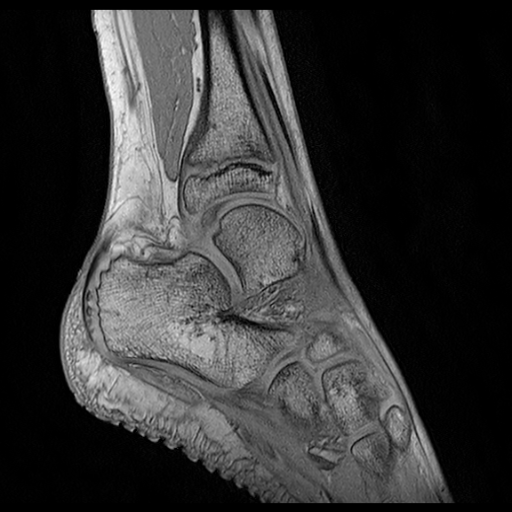

Fig. 2: Visual comparison of UNet regularization methods: baseline UNet [2], adversarial regularization [6], shape priors based regularization [7] and the proposed shape priors based adversarial regularization on ankle dataset. Ground truth delineations are in red (). Predicted bones, calcaneus, talus and tibia respectively appear in green (), blue () and yellow ().

Experiments were conducted on two pediatric datasets previously acquired using a 3T Philips scanner [4]. The two MR images datasets were independently acquired on two musculoskeletal joints (ankle, shoulder) from a cohort of 17 and 15 pediatric patients. An expert (12 years of experience) annotated images to get ground truth contours of calcaneus, talus and tibia for ankle, as well as scapula and humerus for shoulder. All axial slices were downsampled to 256×\times256 pixels.

We compared the proposed shape priors based adversarial regularization method (SPAR in Fig.1) with baseline UNet (Base. UNet) [2], adversarial regularization (Adv. Reg.) [6] and shape priors based regularization (Sh. Reg.) [7]. For all methods, the backbone UNet architecture and all training hyper-parameters remained the same. All networks were trained from scratch with randomly initialized weights.

From the quantitative results (Tab.1), our method achieved competitive results compared to state-of-the-art on both datasets. On ankle dataset, our approach ranked best in Dice (92.7%percent\%), RAVD (8.0%percent\%), ASSD (0.8mm) and MSSD (8.1mm) metrics. For shoulder dataset, our method outperformed other approaches in RAVD (13.6%percent\%) while remaining second best in Dice (0.3%percent\% lower than the best) and ASSD (0.3mm higher than the best). We suspected that the high variability observed in shoulder results was due to the poor quality of two outlier examinations. The visual comparisons (Fig.2) provided the evidence of gradual improvements in segmentation quality of the regularized methods over baseline UNet. We wanted to report statistical significance tests to compare the performance of the employed methods but the required sample size determined using a power analysis (with typical statistical power β=0.8𝛽0.8\beta=0.8) was larger than our available datasets.